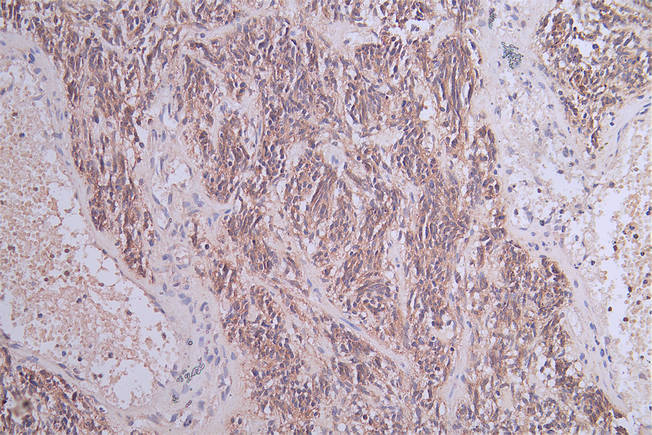

• IHC image of CSB-RA121182A0HU diluted at 1:100 and staining in paraffin-embedded human glioma cancer performed on a Leica BondTM system. After dewaxing and hydration, antigen retrieval was mediated by high pressure in a citrate buffer (pH 6.0). Section was blocked with 10% normal goat serum 30min at RT. Then primary antibody (1% BSA) was incubated at 4°C overnight. The primary is detected by a Goat anti-rabbit polymer IgG labeled by HRP and visualized using 0.05% DAB.